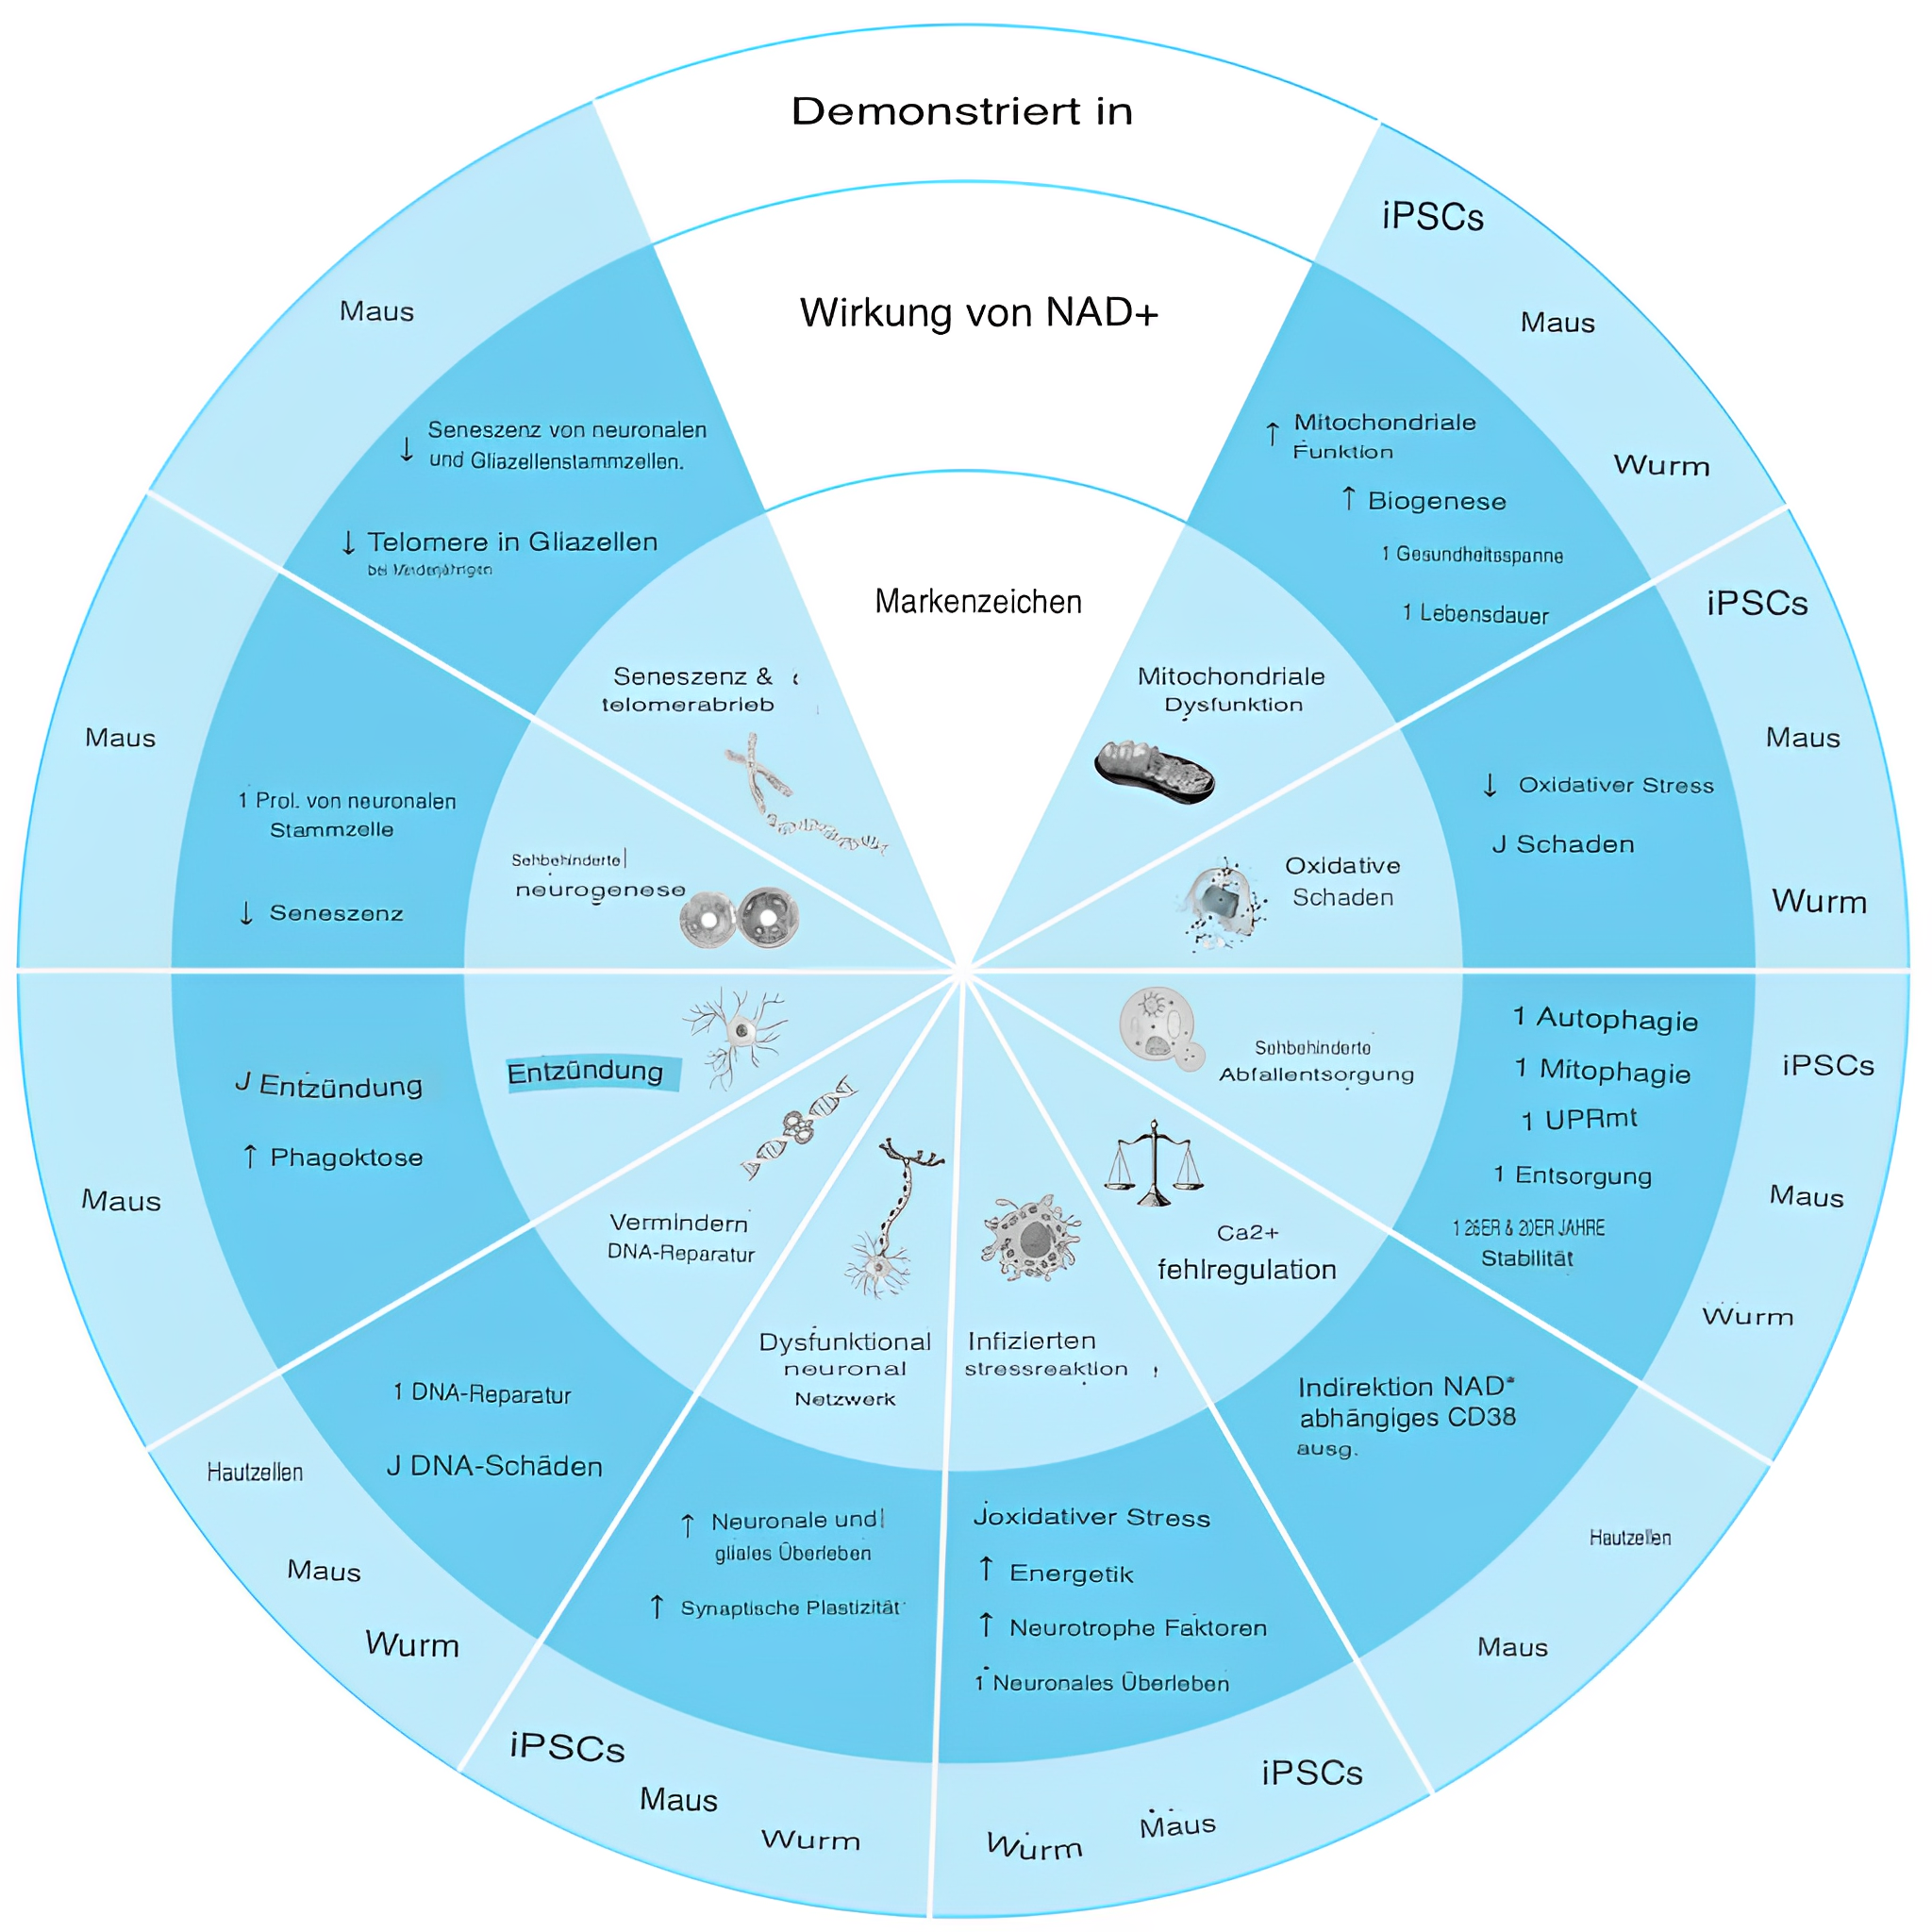

Im Jahr 2018 postulierte eine in Cell Metabolism veröffentlichte Übersicht 10 Kennzeichen der Gehirnalterung, zu denen die folgenden Veränderungen gehören:

•Mitochondriale Dysfunktion

•Akkumulierte oxidative Schäden in Zellen

•Beeinträchtigte zelluläre Abfallbeseitigung

•Seneszenz (Tod) von Nerven- und Gliazellen

•Beeinträchtigte Stressreaktion

Es sind weitere klinische Untersuchungen erforderlich, aber laut der Übersicht „entdecken neue Erkenntnisse Zusammenhänge, durch die altersbedingter NAD+-Mangel positiv mit den 10 Kennzeichen der Gehirnalterung zusammenhängt.